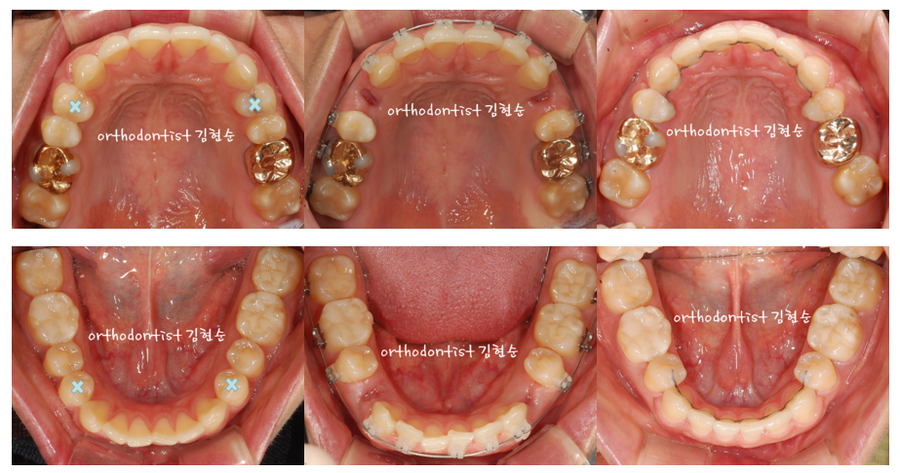

- 아래 좌측 사진들의

하늘색 X 작은 어금니들,

(위 2개 치아, 아래 2개 치아)

총 4개의 치아를

먼저 발치합니다.

좌측이 세라믹 교정 전,

가운데가 발치 후 교정 시작,

우측이 교정 마무리

단계의 사진들입니다.

- 앞니의 각도를 유지하기 위해

가운데 사진들의

발치한 빈 공간으로

치아를 천천히 이동시킵니다.